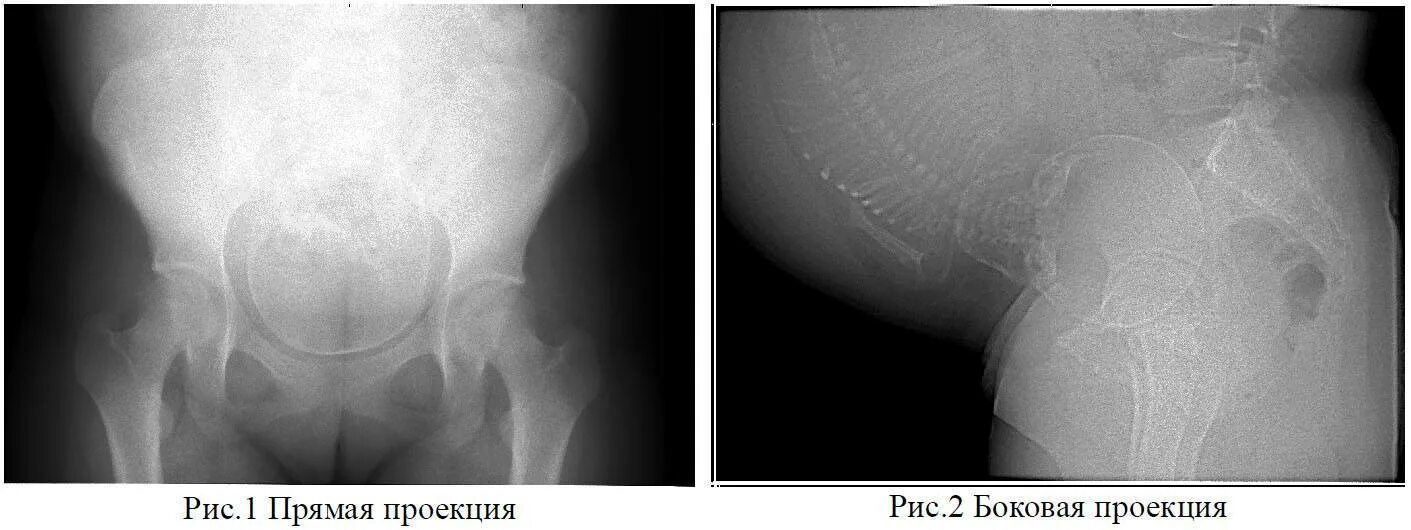

Сделала флюорографию будучи беременной